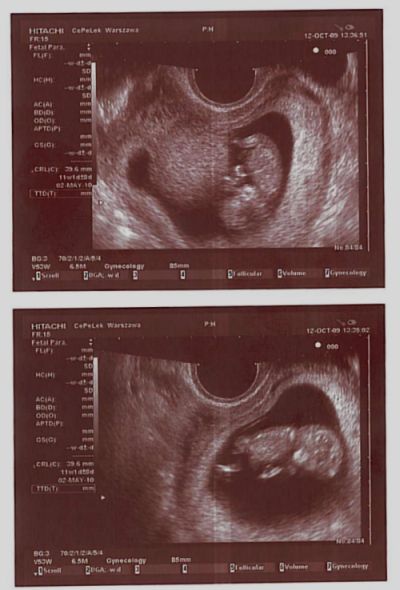

bpoisoncat:

4cm brykajacego stworka :)

Pobierz obrazek (37.3kiB)